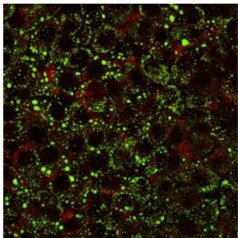

Intracellular lipid content was quantified using Nile red staining. HepG2 cells (250,000) were seeded in a six-well microplate and subjected to fatty acid treatment for 24 hours. Following treatment, cells were washed, permeabilized, and fixed under sterile conditions. Lipids were stained with Nile red (0.5 μg/mL), a fluorescent dye with solvatochromic properties, allowing dual emission spectra to distinguish neutral and polar lipids. Fluorescence was captured using an LSM 800 confocal microscope equipped with a 40×/1.3 objective lens, with excitation/emission wavelengths of 495/519 nm and 594/618 nm. All staining procedures were conducted at room temperature, with samples shielded from direct light to prevent photobleaching.

To evaluate the effect of ACTIVE ENERGY on human cells, an in vitro model was established. This model replicated hyperlipidemic conditions by exposing HepG2 cells to a 2:1 molar ratio of oleate and palmitate, bound to 1% BSA, yielding a 6:1 fatty acid-to-BSA molar ratio. While fatty acid exposure at a concentration of 0.6 mM for 24 hours led to significant intracellular lipid accumulation, cell exposure to ACTIVE ENERGY importantly decrease the presence of lipid droplets in the cell cytoplasm.

Confocal microscopy confirmed an increase in cytoplasmic lipid droplets in response to fatty acid treatment (figure 1A).

At a concentration of 0.6 mM, lipid droplet internalization was already evident, with a greater abundance compared to control cultures (figure 1B).

Notably, when 0.5% ACTIVE ENERGY was added to the culture medium, a marked reduction in intracellular lipid content was observed (figure 1C), with levels approaching those seen in untreated control cells.

These findings show that when 0.5% ACTIVE ENERGY is incorporated in the cell culture media, it can be observed a decrease in cell lipid content (figure 1C), close to the observation found in control cell cultures. In order to continue understanding this effect linked to an increased cell catabolism, further studies are being performed.

Figure 1a.

Figure 1b.

Figure 1c.